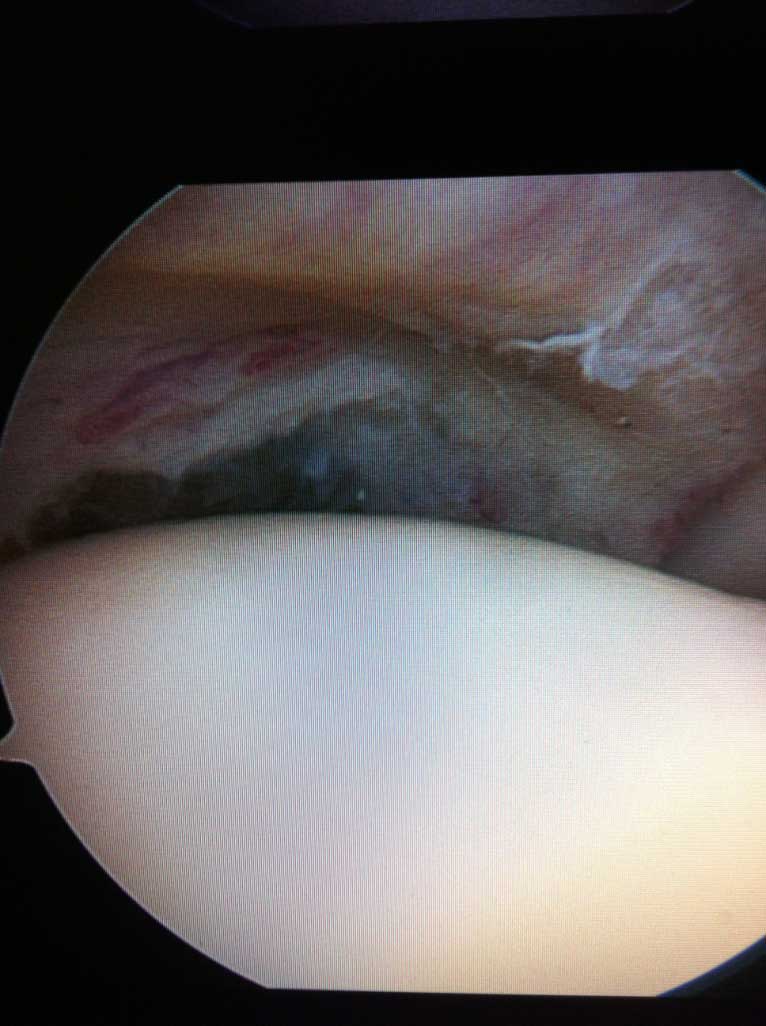

Wie auf der Bilddokumentation ersichtlich, wird die Kontaktfläche zwischen der kleinen knöchernen Pfanne und dem Kopf durch einen knorpeligen Ring, s.g. Labrum, der sich am Pfannenrand befindet, vergrössert.

Ähnlich wie in anderen Gelenken, sorgen auch in der Schulter die s.g. passiven und aktiven Stabilisatoren für das Zusammenhalten der zwei o.g. knöchernen Gelenkpartnern ( Kopf und Pfanne ).

Die passiven sind die Gelenkkapsel und Bänder. Diese ermöglichen dank enormer Dehnbarkeit ein sehr grosses Bewegungsausmaß der Schulter.

Die aktiven Stabilisatoren sind die gelenkübergreifenden Sehnen, welche in Form d.s.g. Rotatorenmanschette, seitlich am Oberarmkopf ansetzen. Deren Aufgabe ist sowohl den OA Kopf in der flachen Pfanne zu zentrieren als auch mit dem Arm in der Schulter zu bewegen.